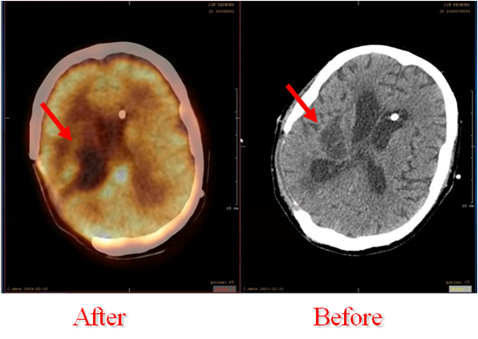

Mr. Redmond underwent NK cells treatment which consisted of either NK cells and/or NK Exos daily. The treatment was administered intracranially through the burr hole left from previous craniectomy combined with intravenous administration. The GBM reduced by a single spot after 30 days. Mr. Redmond is more aware of his surrounding, more responsive, and showed better cognitive response.